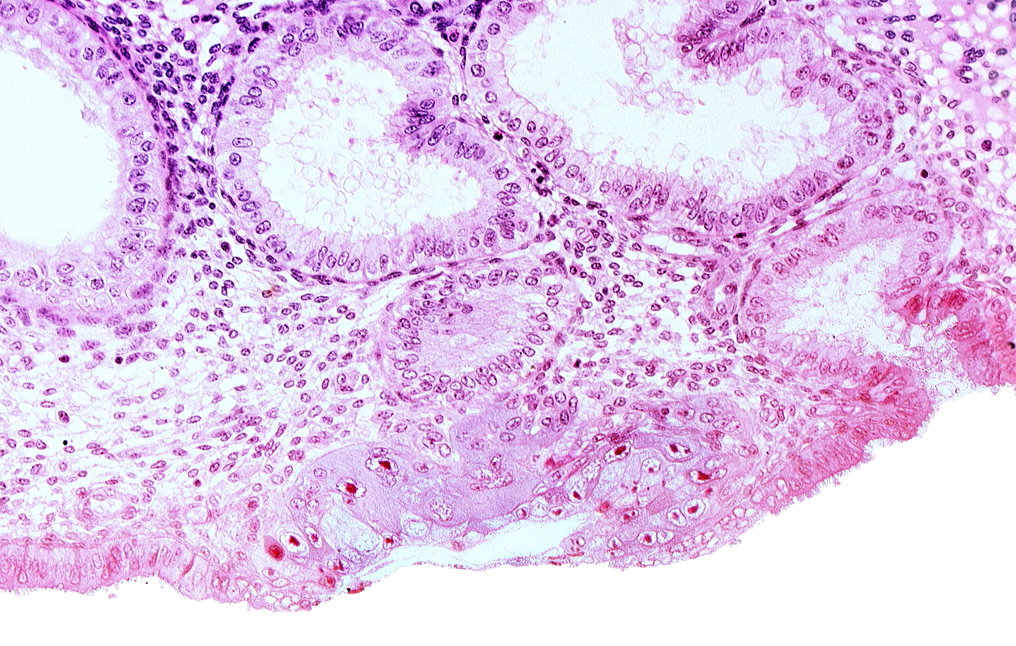

Carnegie Embryo #8020 | Location: 05-06-06

Keywords: blastocystic cavity (blastocoele), endometrial gland, extra-embryonic mesoblast, lumen of endometrial gland, membranous trophoblast at abembryonic pole, mouth of endometrial gland, uterine cavity

Source: The Virtual Human Embryo.